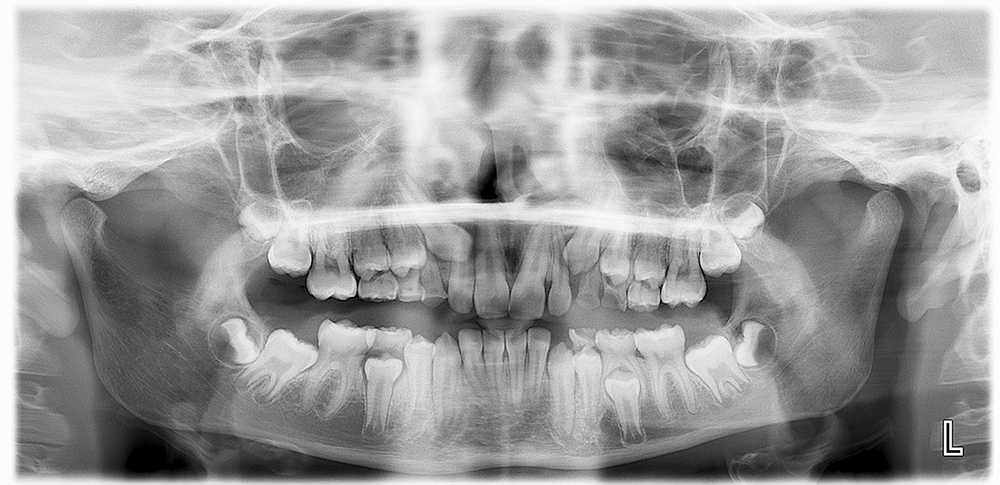

Une radio panoramique dentaire est un cliché radiographique de l'ensemble de la denture et des articulations temporo mandibulaires.

Toutes les dents sont donc visibles sur le même cliché ainsi que :

- Les arcades dentaires

- Les maxillaires supérieurs et inférieurs

- La partie basse des fosses nasales

- Le plancher des sinus maxillaires

En plus de l'étude des soins déjà effectués, ou à effectuer, sur les dents (traitement de caries, couronnes…), la panoramique dentaire permet de dépister les problèmes éventuels des dents, des maxillaires et des sinus, en particulier :

- Les caries

- La position des dents de sagesse dans les maxillaires

- L'existence de kystes dentaires à l'extrémité des racines

- Les dents surnuméraires

- Les agénésies dentaires (absence des germes des dents)

- L'évaluation générale de la perte de l'os de soutien des dents (parodontite)

- Les tumeurs

L’examen permet également de localiser l'emplacement des cavités naturelles (avant d'envisager la pose d'un implant dentaire par exemple) et le trajet du nerf mandibulaire.

Chez l'enfant, la panoramique dentaire permet de visualiser les germes des dents définitives, c'est-à-dire des futures dents de l'adulte. Ceci autorise l'évaluation de l'âge dentaire.

L’on peut voir aussi les agénésies (absence des germes des dents).

La panoramique dentaire est donc un outil de diagnostic souvent indispensable qui permet la planification du traitement du patient.